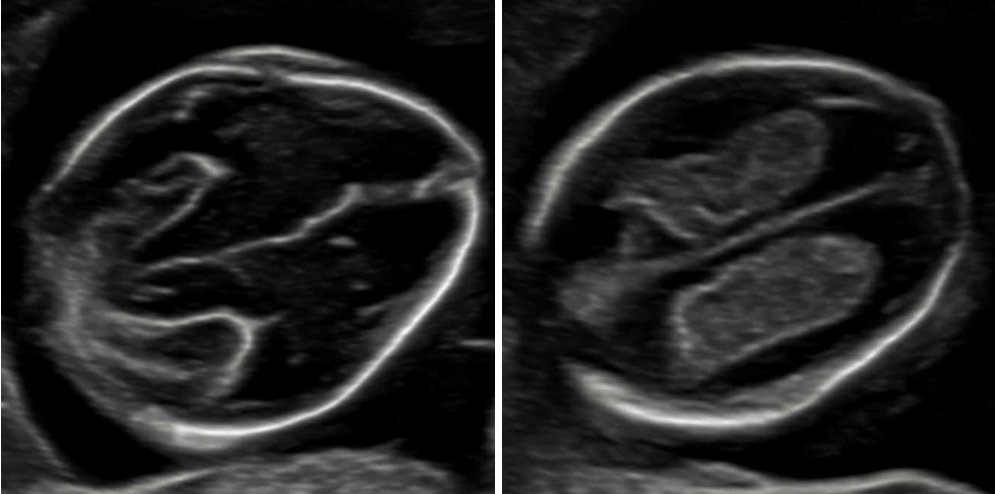

„Feindiagnostik“: 20-24 SSW

Wir schauen Ihr Kind im Ultraschall detailliert von Kopf bis Fuß an. Mit Fortschreiten der Schwangerschaft liegt der Fokus hier besonders auf der Entwicklung von Herz und Kopf Ihres Kindes. So können wir Besonderheiten frühzeitig erkennen, die Schwangerschaft optimal begleiten und die Geburt bestmöglich vorbereiten. In manchen Fällen ist eine Behandlung bereits während der Schwangerschaft möglich.

Je nach Fragestellung kann diese Untersuchung auch zu einem deutlich früheren oder späteren Zeitounkt sinnvoll sein.